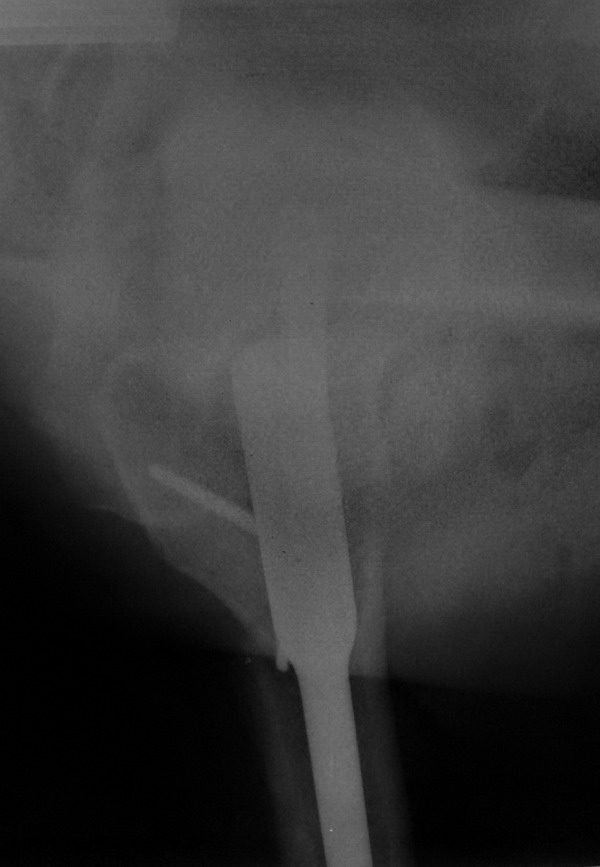

Так стало после реостеосинтеза - два снимка непосредственно сразу после

операции, последний снимок - через 6 мес. Пациент свободно ходит.